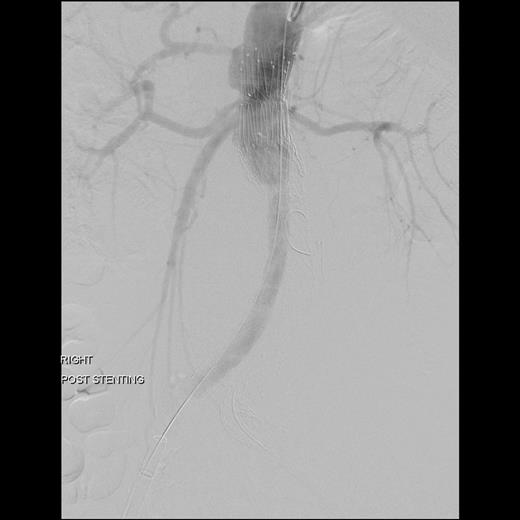

An 81-year-old gentleman with a background of ischaemic heart disease, hypertension, hyperlipidaemia, polycystic kidney disease and previous right hemicolectomy for bleeding diverticular disease, underwent EVAR 10 years ago. He was on yearly follow-up with computed tomography (CT) scan and latest CT in 2012 showed a type III endoleak with aneurysmal sac of 10 cm in size. Both common iliac arteries were long and tortuous. He was electively admitted for a diagnostic calibrating aortogram in our CT hybrid angiography suite (Toshiba Infinix VC-i). Intra-operatively, digital subtraction angiography (Fig. 1) showed significant type IIIa endoleak with component separation on the left iliac limb. The old stent graft was <20 mm away from the left renal artery proximally (lowest visceral artery). He was discharged the next day and re-admitted 2 weeks later for a staged operation. Decision was made for a combination of left renal artery chimney, aortouniiliac stent grafting and femorofemoral crossover bypass.

Digital subtraction angiography showing significant type 3a endoleak with component separationon the left iliac limb (black arrow). Both common iliac arteries were long and tortuous.

Surgery was performed in hybrid operating theatre. The aorta was accessed via bilateral groin cut-downs to expose both common femoral arteries. Intra-operatively, the type IIIa endoleak was excluded using a right-sided Cook aortouniiliac stent graft (AX1-1-36-116). The left renal arteries were cannulated from the left brachial artery. A PTFE-covered nitinol stent (Atrium V12) was advanced into the left renal artery and deployed in a chimney fashion. The left iliac limb of the stent was occluded using a 20 mm Amplatzer plug proximally and distally with Iliac Plug Zip 24 and 30 mm. Femorofemoral crossover bypass was then performed to complete the surgery. The completion angiography showed adequate sealing with no endoleak (Figs 2 and 3).

The completion angiography showed adequate sealing with no endoleak.